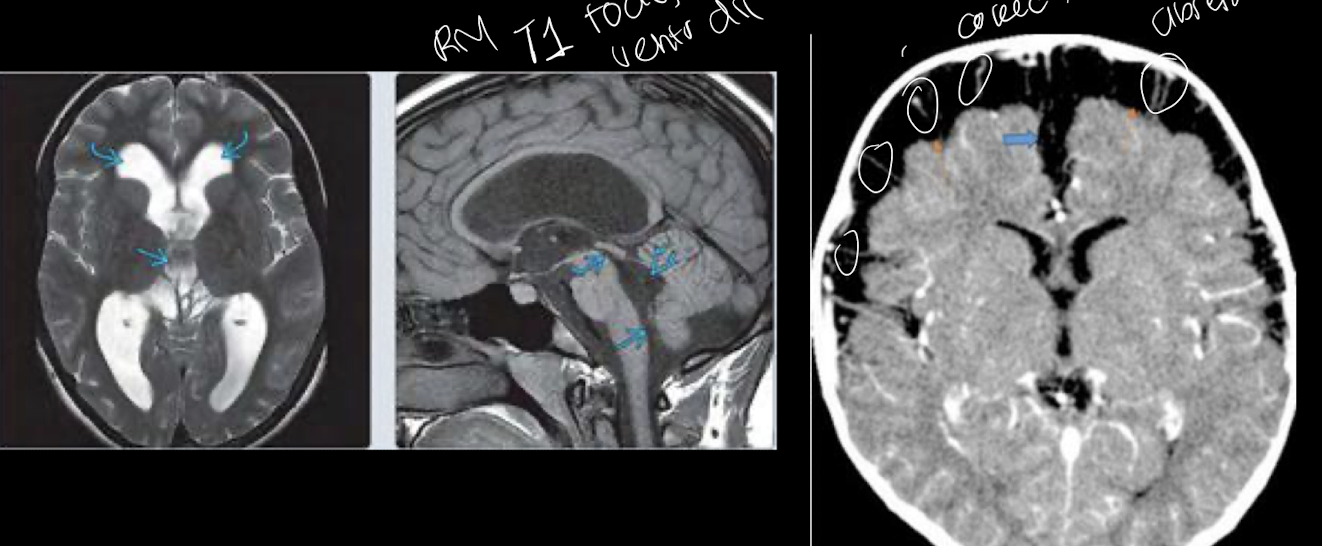

12

Q

A

HCEV